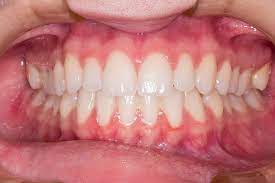

치주염 증상

치주염(Periodontitis)은 입안 건강에 영향을 미치는 질환으로, 다양한 증상을 보일 수 있습니다. 아래에 치주염의 주요 증상을 자세히 설명해 드리겠습니다:

1. 잇몸 출혈: 가장 흔한 치주염 초기 증상 중 하나는 잇몸 출혈입니다. 칫솔질, 치실 사용, 또는 딱딱한 음식을 먹을 때 잇몸이 출혈할 수 있습니다. 잇몸 출혈은 염증으로 인해 잇몸 조직이 약화되고 혈관이 더 가시적으로 되기 때문에 발생합니다.

2. 치아 주위 붓기: 치주염이 진행되면 잇몸 주위 조직이 붓게 됩니다. 이로 인해 잇몸이 붓고 부풀어오르며 거의 항상 충혈된 상태를 유지합니다.